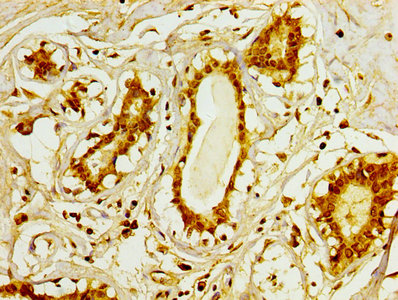

IHC image of CSB-PA025554LA01HU diluted at 1:100 and staining in paraffin-embedded human colon cancer performed on a Leica BondTM system. After dewaxing and hydration, antigen retrieval was mediated by high pressure in a citrate buffer (pH 6.0). Section was blocked with 10% normal goat serum 30min at RT. Then primary antibody (1% BSA) was incubated at 4°C overnight. The primary is detected by a biotinylated secondary antibody and visualized using an HRP conjugated SP system.

IHC image of CSB-PA025554LA01HU diluted at 1:100 and staining in paraffin-embedded human breast cancer performed on a Leica BondTM system. After dewaxing and hydration, antigen retrieval was mediated by high pressure in a citrate buffer (pH 6.0). Section was blocked with 10% normal goat serum 30min at RT. Then primary antibody (1% BSA) was incubated at 4°C overnight. The primary is detected by a biotinylated secondary antibody and visualized using an HRP conjugated SP system.